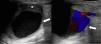

Se realiza ecografía (fig. 1) y angio-TAC (fig. 2), diagnosticándose como aneurisma poplíteo gigante. Ecocardiograma y estudio oftalmológico normales. Se interviene de forma preferente (fig. 3), con colocación de injerto de vena safena invertida.